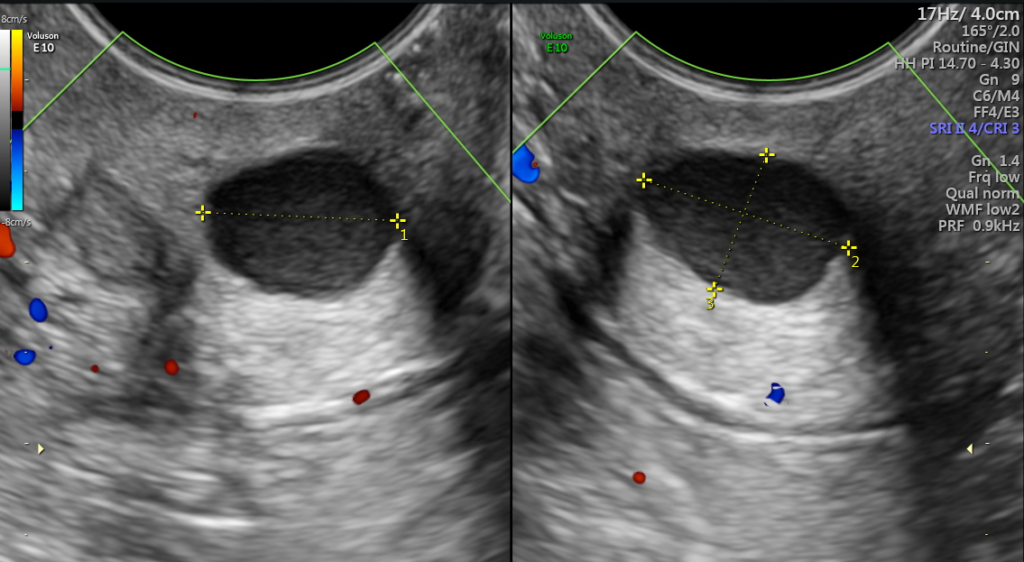

nabothian cyst in cervix II Dr Nasrin Fatema II Realtime Ultrasound II nabothian cyst in TVS

Ultrasound and Color Doppler videos Multiple Nabothian cysts of the cervix

CISTO DE NABOTH NO COLO DO ÚTERO PELO ULTRASSOM TRANSVAGINAL Saiba aqui o SIGNIFICADO! YouTube

Mulher com 44 anos de idade com quistos de Naboth. a) No plano sagital… Download Scientific